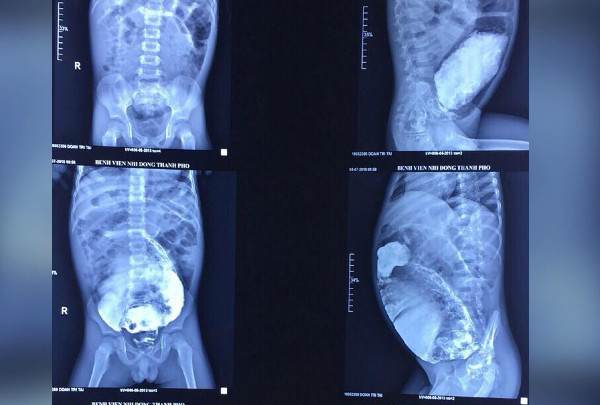

| Đại tràng của bé giãn to, ứ đầy phân. |

Bác sĩ chẩn đoán bé bị hội chứng phình đại tràng bẩm sinh (Hirschsprung), khiến một đoạn đại tràng không có dây thần kinh để kiểm soát sự co bóp. Với sự tham vấn từ phó giáo sư Trương Nguyễn Uy Linh, các bác sĩ tiến hành 3 giờ mổ cắt bỏ phần trực tràng bị phình dài gần 20 cm, giãn to 20 cm. Dù đã được thụt tháo bơm rửa trước mổ nhưng lượng phân ứ đọng bên trong vẫn còn gần 3 kg. Sau hơn 15 ngày điều trị, hiện bé ăn uống và tự đi tiêu thoải mái, bụng xẹp hẳn, vừa xuất viện.